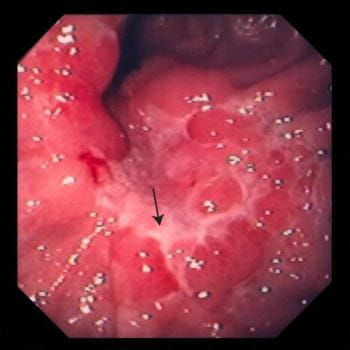

- 위암 초기증상 : 위축성 위염

위축성 위염이 있으면 위암에 걸릴 확률이 6배 더 높다고 합니다. 또는 이미 위축성 위염이 발생했다면 위가 다시 정상적으로서 회복되지 않을 수 있어요. 따라서 일정 기간 동안 내시경 검사를 통해 후속 조치를 취하는 것이 필요합니다. 짠 식품을 피하는 것도 매우 필요합니다. 위축성 위염은 위산 분비가 눈에 띄게 떨어뜨리여 소화 행동이 저하돼요. 또는 위암으로써 이어지는 것은 위 점막 세포의 변형이라고 해요.